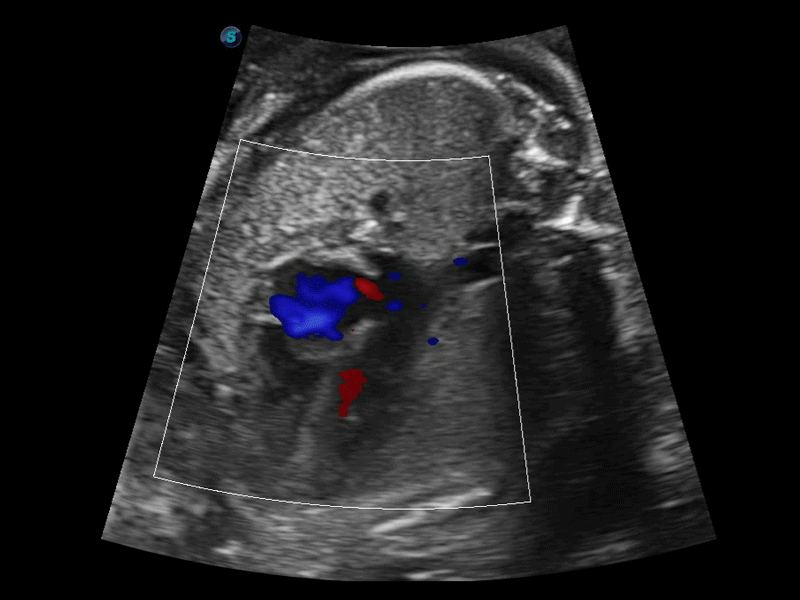

造影成像

造影成像功能和定量分析工具包使医生能够更好的评估血流灌注情况。独特的动态声压控技术有效控制造影剂的声压,保证更长的造影剂持续时间,更好的观察病变灌注的延迟相位。